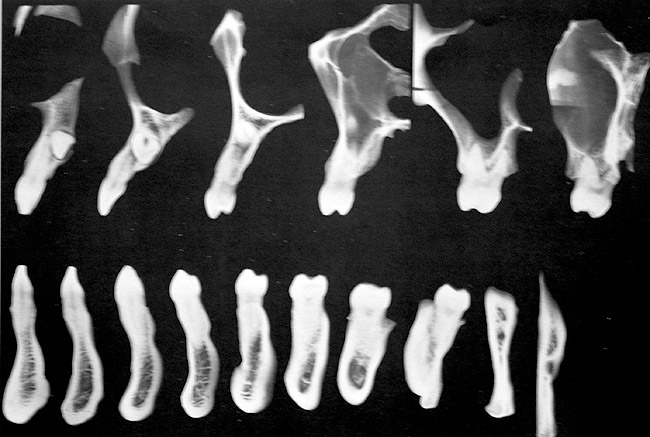

Figure 6  Tomograms showing natural teeth alignments on their bony bases (Wheeler R. Dental Anatomy, Physiology and Occlusion. 5th ed. Philadelphia, PA: WB Saunders; 1974:364).

Figure 6

Another concern for loading of dental implants is implant alignment. When placing implants for the edentulous patient and an overlay or hybrid restoration is planned, the implants should then be placed as parallel as possible and slightly lingual to the actual tooth position. This allows establishment of normal contours of the prostheses and space for placement of the prosthetic teeth. Implants should not be placed in the central incisor region for a maxillary overlay prosthesis because this will compromise palatal contours, thereby affecting speech and tongue function. If, however, implants are planned for the partially edentulous patient and the replacement is for a natural tooth or teeth, then implants should be placed more in line with the long axis of the natural root. Teeth are designed to better handle the multitude of directional loads encountered during mastication when properly aligned on their bony base. Implants placed more in line with natural tooth roots that are properly positioned on their bony base may allow implants to better endure the various functional loads while promoting the continual physiologic bone remodeling necessary for long-term implant survival (Figure 6 and Figure 7). Depending on the type of anticipated function and the presence or signs of parafunctional habits, use of a maxillary biteplane/nightguard may be indicated (Figure 8). This can reduce the possibility of lateral loads, which have a detrimental effect on the dental implant(s). The biteplane is adjusted in centric relation with simultaneous occlusal contacts and shallow anterior guidance.